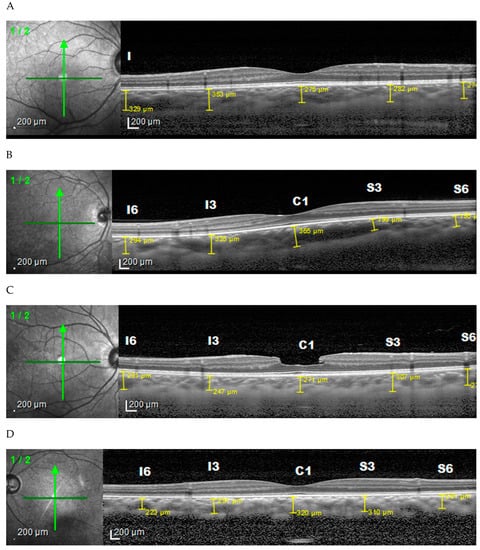

2. Materials and Methods

2.2. Ophthalmology Examination